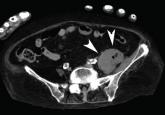

A cancer patient receiving corticosteroids for a brain metastasis developed emphysematous cystitis and psoas muscle abscess.

A 52-year-old woman with diabetes mellitus presented with a 1-month history of pain in the right lower abdomen and right back. Although she had a fever when the pain started and her pain was aggravated by walking, her pain and fever had gotten better after taking antibiotics prescribed earlier.

The patient was admitted to the hospital for percutaneous drainage, which produced 26 mL of pus on the first day and 320 mL on the next day; culture was positive for Escherichia coli. Urine culture was also positive for E coli; blood culture was not. We concluded that these results were secondary to pyelonephritis.

Inflammatory markers such as erythrocyte sedimentation rate and C-reactive protein may be elevated in all patients with iliopsoas abscess, so if those markers are not elevated, we may have to consider other conditions such as cancer.1 Computed tomography is nearly 100% sensitive for iliopsoas abscess and is the gold standard for diagnosis.3